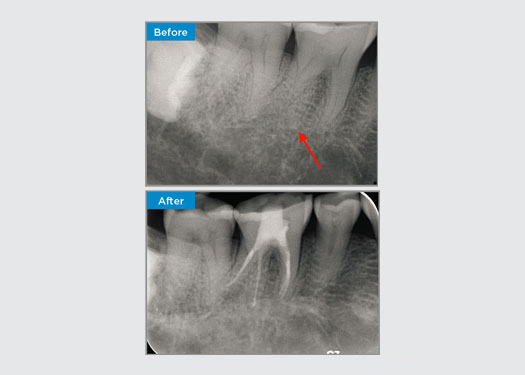

El paciente presentó periodontitis apical asintomática en la pieza dental 34. A partir de la radiografía preoperatoria, se observó que la pieza dental 34 tenía dos raíces visibles. Sin embargo, un escaneo CBCT confirmó un premolar de tres raíces y los canales se dividieron en tres en la raíz media. Una cuidadosa selección de limas es fundamental para este diente delicado.

En esta situación, la preservación de la estructura del diente/raíz es esencial para reducir el riesgo de reborde, transporte, cierre, perforación y fractura de la raíz. La selección de casos, el diagnóstico y la planificación previa al tratamiento son importantes. La selección de limas de endodoncia con flexibilidad, eficiencia y respeto por la anatomía de la raíz natural es fundamental.